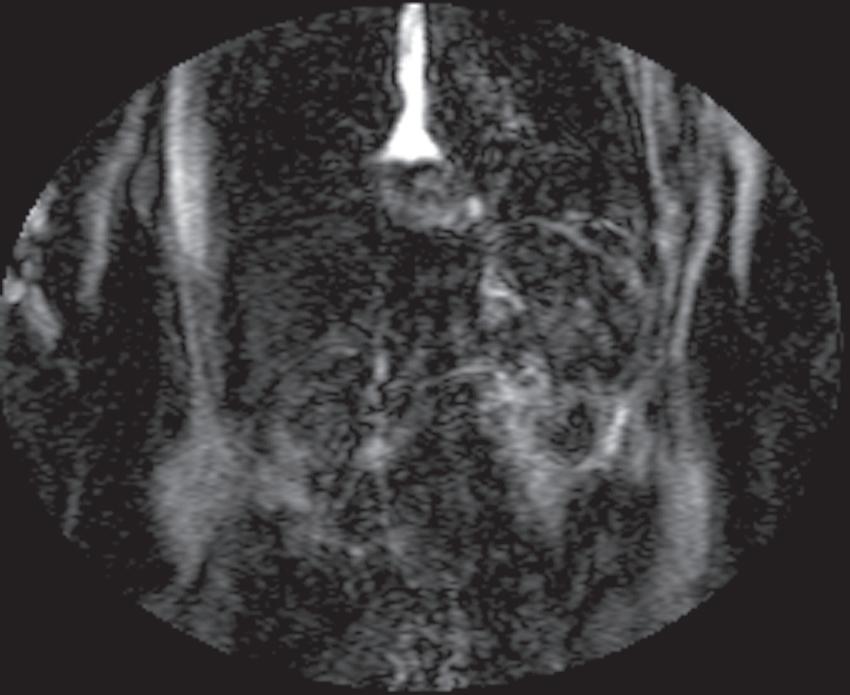

Real-time viewing of contrast transit (Bolus Track, Philips; CARE Bolus, Siemens; SmartPrep, GE; VisualPrep, Toshiba) involves careful monitoring by the technologist of serial large field-ofview (FOV) GE images after administration of the entire bolus of contrast (see Fig. 1.17). Transit of gadolinium through the superior vena cava (SVC) into the right heart through the pulmonary circulation and from the left heart into the aorta is portrayed on the monitor cinegraphically. With impending arrival of contrast into the abdominal aorta, the technologist instructs the patient to suspend respiration in preparation to acquire the arterial phase images. Portal phase images (or

FIG. 1.17 Example of Bolus Track timing sequence to initiate the dynamic acquisition. Selected serial coronal large field-of-view gradient-echo images obtained immediately after the intravenous administration of gadolinium (A–D) reveal the inflow of gadolinium into the superior vena cava (SVC; A), the right ventricle (B), through the pulmonary outflow tract and into the pulmonary arterial system (C), and into the thoracic aorta, down the abdominal aorta (D).